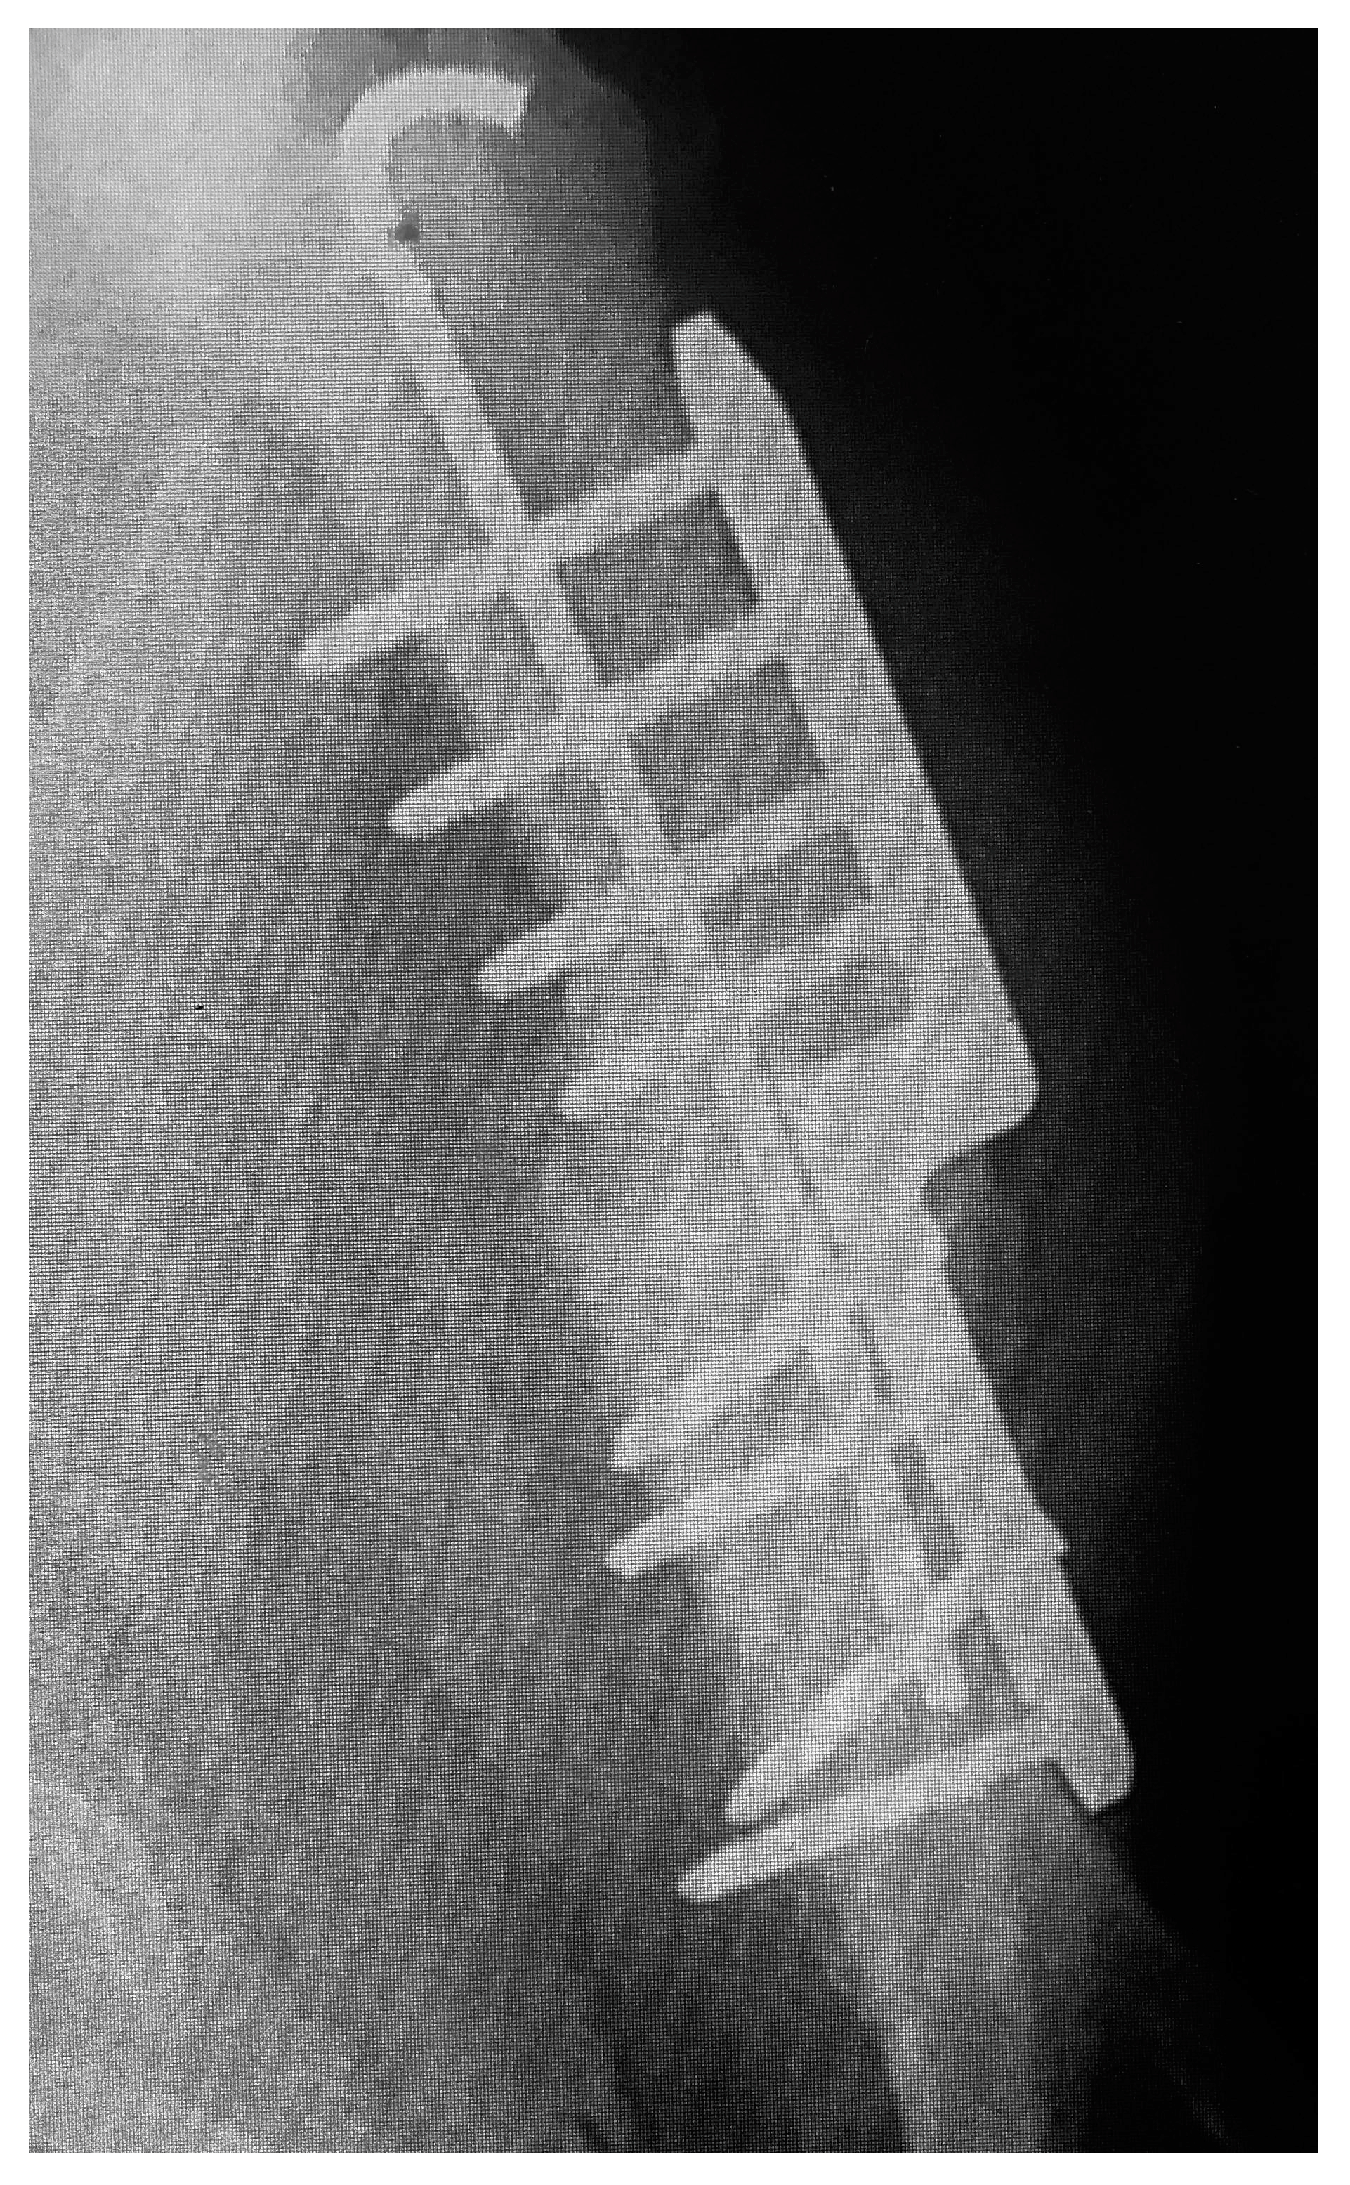

Clinical examinations were also performed at 2, 6, 8, 12, and 14 weeks after surgery. Radiographs of the elbows were taken pre- and post-operative at 6 and 12 weeks (Figure 2 and Figure 3). The owners were asked to assess the dog using a telephone questionnaire (Canine Brief Pain Inventory).

Figure 2. Post-operative view of the repair.